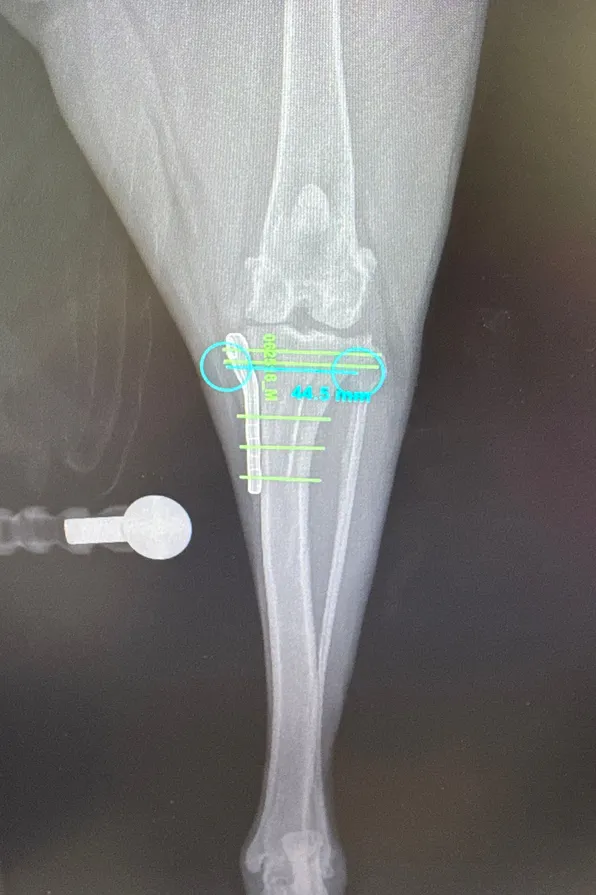

Caring Animal Hospital now offers a variety of orthopedic procedures, including tibial plateau leveling osteotomy (TPLO) for the treatment of cranial cruciate ligament (ACL) disease in dogs, trochlear groove deepening and tibial tuberosity transposition for patellar (kneecap) luxation, limb amputation, femoral head and neck ostectomy (FHO), and select fracture fixation procedures.

Casey, our Head Technician, and Dr. Hailee Cotter have completed advanced, specialized training at Colorado State University’s prestigious Translational Medicine Institute, receiving instruction in fracture repair and TPLO surgery from leading board-certified orthopedic surgeons. This advanced training allows us to deliver a higher caliber of orthopedic care to our patients right here at home.

We provide advanced orthopedic care for conditions such as cruciate ligament injuries, fractures, patellar luxation, joint abnormalities, hip conditions, and more. Using modern surgical techniques, thorough pre-surgical planning, and attentive post-operative care, we focus on safe healing and a smooth recovery. We work closely with pet owners at every step—clearly explaining options, answering questions, and creating individualized treatment plans to restore mobility and alleviate pain.

TPLO